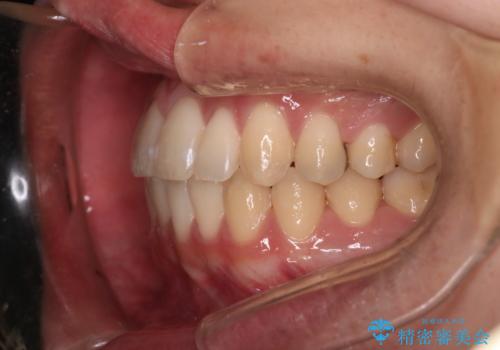

気にされていた八重歯とがたつきが綺麗に改善されました。

非抜歯矯正だったこともあり、1年半以内という短い期間で矯正を終了することができました。